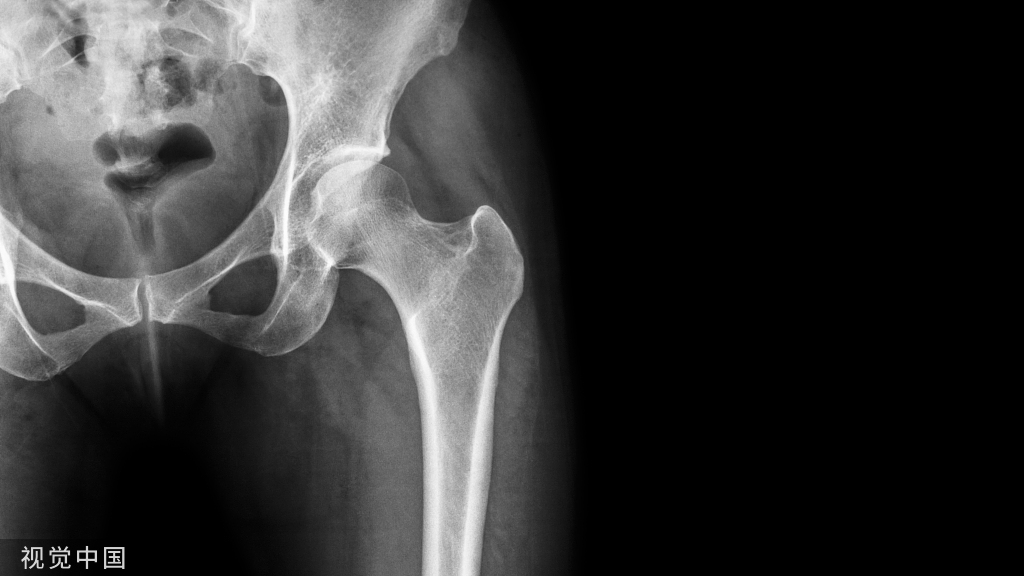

【普通放射图片】:

【影像表现】:X线平片(A、B)示骨小梁减少、变细,骨密度减低,骨皮质变薄。【影像诊断】:骨质疏松。